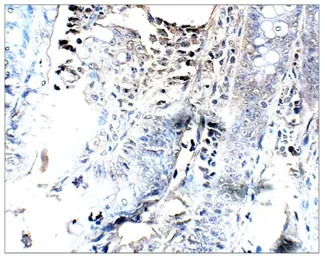

IHC-P analysis of baboon colon tissue using GTX47870 PGAP3 antibody (Internal).

Dilution : 1:100